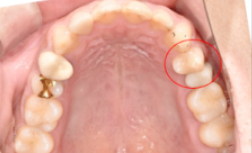

After : 임플란트 후

2021.07.16 / 2021.10.21

임플란트 최종 보철물 식립 후의 사진입니다.

Before / After : 임플란트 전/ 후

2021.07.16 / 21.10.21

임플란트 전, 후의 최종 사진입니다.

치아가 잘 식립된 걸 확인하실 수 있습니다.^^